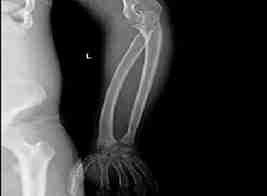

图3肋骨呈“飘带状”,胧骨端肥大肩关节间隙增宽,胧骨头向下移位

图7胧骨干角稍增大,呈胧外翻

图8尺挠骨远端相对关节面斜形改变

图9左侧股骨远端、胫骨近端骨端肥大